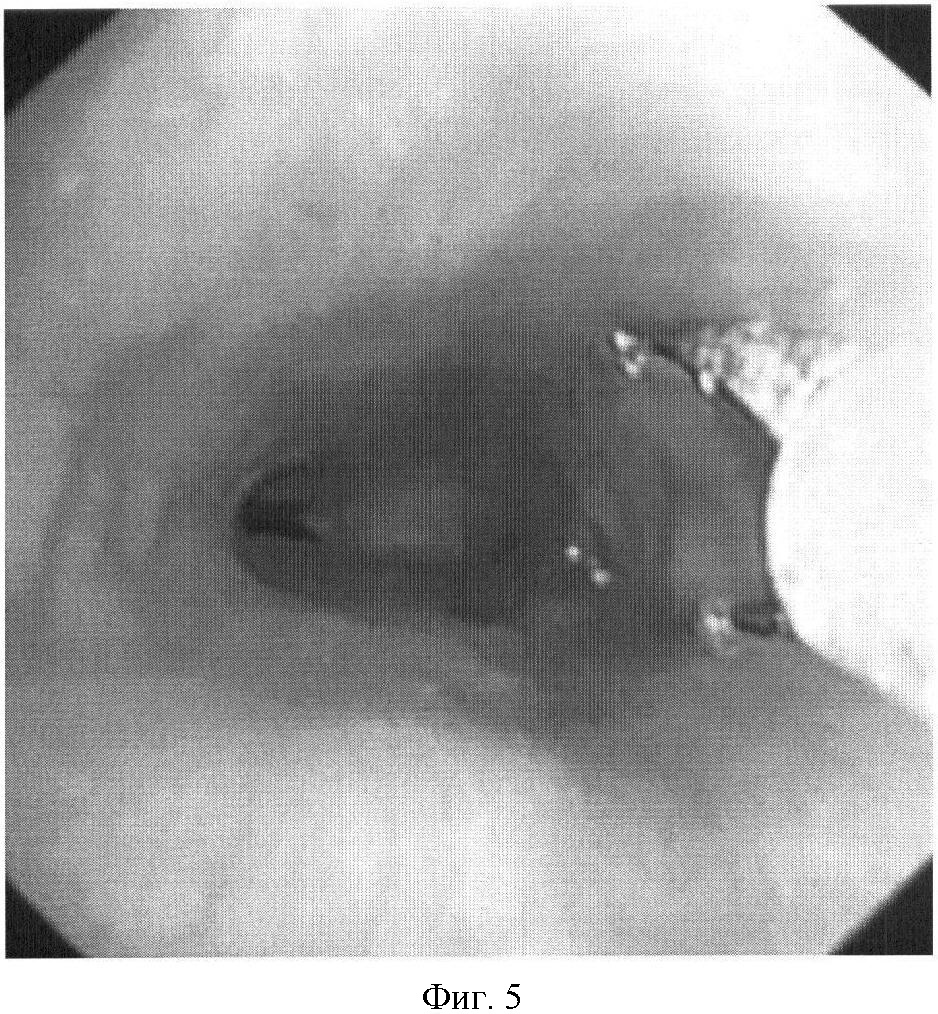

На фиг.1 представлена рентгенограмма пищевода с контрастным веществом: определяется контрастирование трахеопищеводного свища. На фиг.2 представлена эндоскопическая картина просвета пищевода: устье трахеопищеводного свища указано стрелкой. На фиг.3 представлена эндоскопическая картина просвета пищевода: предварительно в устье трахеопищеводного свища, открывающегося в просвете трахеи, было ведено 0,8 мл красящего вещества (метиленовой сини), после этого в просвете пищевода определяется прокрашивание устья трахеопищеводного свища (указано стрелкой). На фиг.4 – пломбирование устья трахеопищеводного свища тахокомбом, предварительно устье свища было последовательно подвергнуто электрокоагуляции и химиокоагуляции (96% этиловый спирт). На фиг.5 – клиппирование запломбированного устья свища. На фиг.6 – контрольная эзофагоскопия, выполненная через 3 месяца после операции: в просвете пищевода в области устья трахеопищеводного свища определяются две скрепки. На фиг.7 – контрольная рентгенограмма после эндоскопического лечения (через 3 месяца): в области трахеопищеводного свища определяется незначительный дефект наполнения (указан стрелкой), трахеопищеводный свищ не контрастируется.